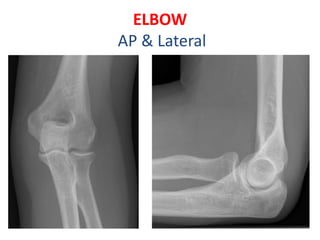

ELBOW

AP & Lateral

• Appearance(Years)

• 1st- Capitulum and lateral

part of trochlea

• 5th – Head of Radius

• 6th- Medial epi. Of

humerus

• 9th- Medial part of

trochlea

• 10th- Top of Olecranon

process

• 12th- Lateral epi. Of

• Fusion

• 15th- Olecranon epiphysis

with upper end of ulna

• 16th – lateral epicondyle,

capitulum and trochlea

into one mass, and with

shaft.

• 17th- Head of radius to

shaft

• 20th – Medial epicondyle

of humerus to shaft

Elbow • Appearance(Years) • 1st-Capitulum and lateral part of trochlea • 5th – Head of Radius • 6th- Medial epi. Of humerus • 9th- Medial part of trochlea • 10th- Top of Olecranon process • 12th- Lateral epi. Of humerus • Fusion • 15th- Olecranon epiphysis with upper end of ulna • 16th – lateral epicondyle, capitulum and trochlea into one mass, and with shaft. • 17th- Head of radius to shaft • 20th – Medial epicondyle of humerus to shaft

i. 6 years:fusion of head with tubercles ii. CRITOE (mnemonic): Count 1-3-5-7-9-11 for age iii. Capitulum: 1 year iv. Radial head: 3 years v. Internal (medial)epicondyle: 5 years vi. Trochlea: 7 years vii.Olecranon: 9 years viii.External (lateral ) epicondyle: 11 years